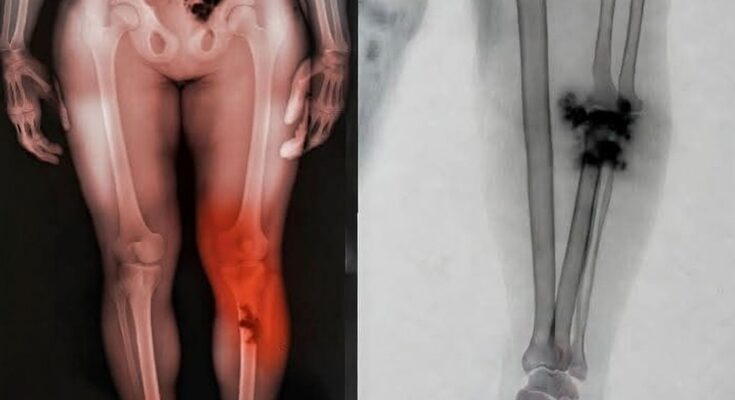

Los síntomas de este nuevo mal que acecha a los “pinchados” son terroríficos porque son silenciosos. Empieza con piquetes en el pecho, luego se te duermen las manos, sientes una neblina mental que no te deja ni sumar dos más dos, y tu sangre… ¡ay, Diosito! Dicen que la sangre se empieza a poner espesa, como chapopote.

- Moretones fantasma: Si amaneces como si te hubiera agarrado a golpes el Canelo y no recuerdas haberte pegado, tu sangre está pidiendo auxilio.